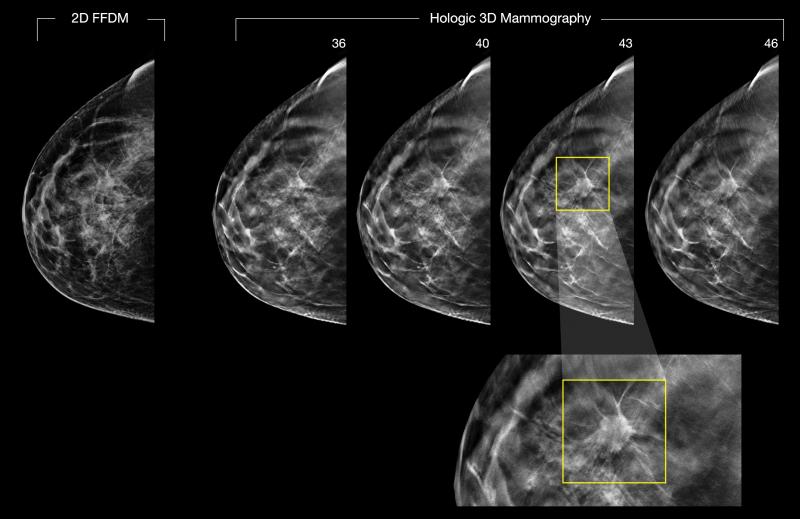

Despite decades of progress in breast imaging, one challenge continues to test even the most skilled radiologists ...

Many mammography practices that use digital breast tomosynthesis (DBT) continue to use dosed digital mammography to ...